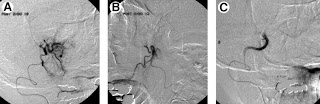

Arterial embolisation